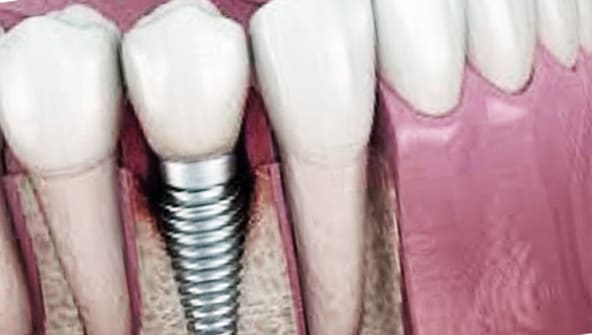

모든 종류의 치아 중에서 어금니는 씹는 데 매우 중요한 역할을 합니다. 그러나 많은 사람들이 어금니의 중요성을 무시하고 충치가 발생하면 조기 치료 없이 치료를 받지 못하는 경우가 많습니다. 어금니를 치료하지 않으면 시간이 지남에 따라 치아의 부식이 증가하여 치아 추출이 필요합니다. 어금니 이식은 어금니를 제거했을 때 받는 시술입니다.

이때 임플란트는 틀니와 달리 자연치와 비슷한 씹는 힘이 있고 잘 유지되면 장기간 사용할 수 있습니다.

어금니에 관한 한 다른 부분과 달리 어금니는 주로 씹는 기능을 담당합니다. 따라서 강한 압력이나 자극을 견딜 수 있는 것이 특징입니다. 어금니 임플란트는 내구성 있는 브랜드를 선택해야 하며 잇몸 뼈, 깊이 및 두께를 고려하여 안정되고 신중하게 시술되야 합니다.